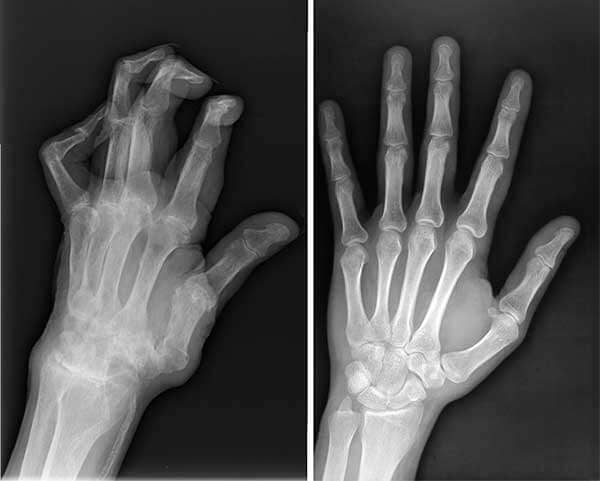

Dokter melihat hasil X-ray, lalu menyuruh saya agar berhenti mengangkat beban berat. Bahkan melarang mengangkat beban melebihi 2 kg!

Hasil X-ray menunjukkan problem serius di persendian lutut saya.

X-ray tangan suami saya, sebelum dan sesudah memakai FlexAmove.

Lihat perbandingannya, sekarang jauh lebih baik.